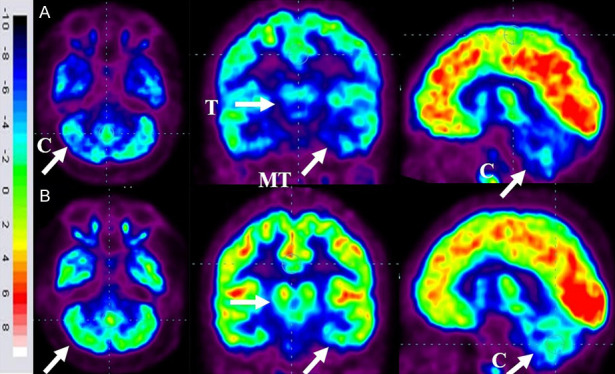

86名患者的家長(zhǎng)同意在干預(yù)6個(gè)月后重復(fù)進(jìn)行FDG-PET CT掃描以進(jìn)行比較分析。干預(yù)前,這些患者的FDG-PET/CT掃描顯示雙側(cè)內(nèi)側(cè)顳葉皮層、丘腦和小腦的代謝活動(dòng)降低[代謝減退]。此外,它們還表現(xiàn)出尾狀頭、殼核、眶額皮質(zhì)和前額葉皮質(zhì)的代謝活動(dòng)增加(代謝亢進(jìn))。

干細(xì)胞移植六個(gè)月后,所有患者的大腦活動(dòng)均得到改善。此前,代謝低下區(qū)域[內(nèi)側(cè)顳葉皮質(zhì)、丘腦和小腦]顯示FDG攝取增加,而代謝亢進(jìn)區(qū)域[尾狀頭、殼核、眶額皮質(zhì)和前額葉皮質(zhì)]顯示FDG攝取減少(圖6)。在進(jìn)行T檢驗(yàn)時(shí),發(fā)現(xiàn)干預(yù)前后這些區(qū)域的平均SUV出現(xiàn)了統(tǒng)計(jì)學(xué)上的顯著變化[P<0.05]。

圖6:ASD患者在細(xì)胞治療前和細(xì)胞治療后6個(gè)月進(jìn)行的FDG-PET/CT大腦掃描的代表性圖像。

A.頂行:標(biāo)有箭頭的藍(lán)色區(qū)域表明代謝低下。B. 下排:用箭頭標(biāo)記的綠色區(qū)域表明細(xì)胞移植后新陳代謝得到改善。

FDG PET CT大腦掃描被用作接受多劑量細(xì)胞移植的患者的額外結(jié)果測(cè)量。它用于監(jiān)測(cè)細(xì)胞水平干預(yù)的效果。這種功能性神經(jīng)影像技術(shù)利用18-FDG來研究大腦的代謝活動(dòng)。我們對(duì)86名患者進(jìn)行了FDG PET CT掃描腦部的比較研究,結(jié)果證明了其對(duì)新陳代謝的平衡作用。代謝低下的區(qū)域顯示代謝增加,而代謝亢進(jìn)的區(qū)域顯示代謝減少。